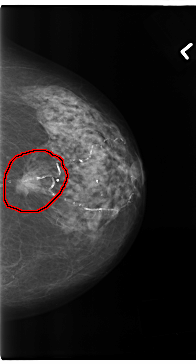

C_0196_1.LEFT_MLO

FILE: C_0196_1.LEFT_MLO.OVERLAY

TOTAL_ABNORMALITIES 1

ABNORMALITY 1

LESION_TYPE MASS SHAPE OVAL MARGINS SPICULATED

ASSESSMENT 5

SUBTLETY 5

PATHOLOGY MALIGNANT

TOTAL_OUTLINES 1

BOUNDARY